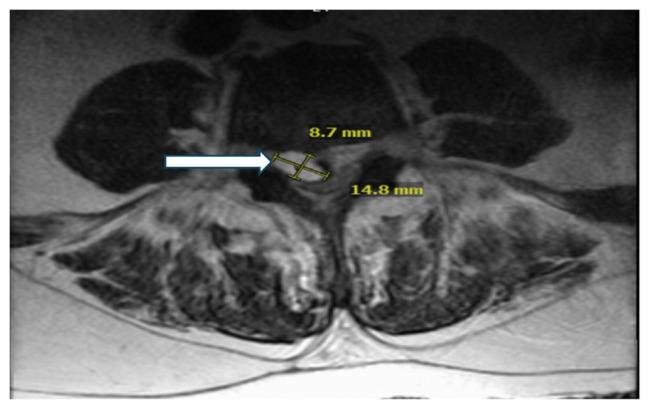

Aerococcus urinae is an alpha-hemolytic gram-positive catalase-negative coccus that typically causes urinary tract infections. It has been rarely implicated in other invasive infections such as endocarditis, bacteremia, peritonitis, meningitis, and vertebral osteomyelitis. There are approximately 50 reported cases of A. urinae infective endocarditis in literature. We present a rare case of a 64-year-old male who was found to have a urinary tract infection, bacteremia, and endocarditis caused by A. urinae.